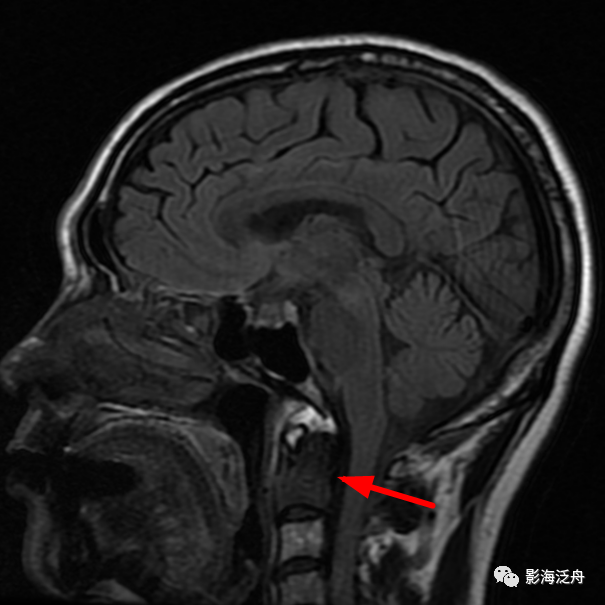

乳腺癌

术后患者,枢椎骨质信号异常,随访证实为骨转移。随着肿瘤患者越来越多,行颅脑MR检查排除脑转移的检查也逐渐增多,不要只顾着在脑子里面找转移灶,周围的结构也应该观察一下。

矢状位上另一个需要观察的就是齿状突的高度,异常增高往往是颅底凹陷症导致的(红线为钱氏线)。